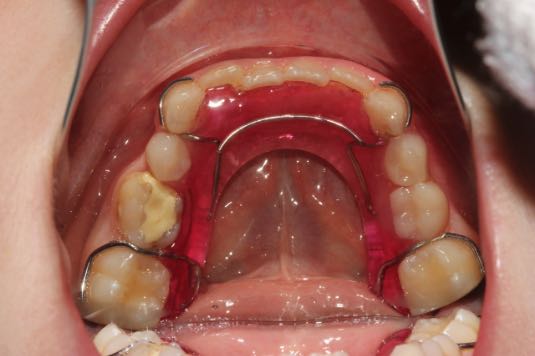

Пластиночные аппараты

Ортодонтические пластины – самый широко известный вид съемных аппаратов. Они могут применяться для детей уже с 8-9 лет. Существует несколько механизмов действий съемных аппаратов, соответственно, они могут применяться в разных клинических случаях.

Как делают съемные ортодонтические аппараты?

Сначала врач проводит осмотр полости рта и опрос пациента, его родителей. Также детский стоматолог может провести различные пробы для уточнения диагноза, назначить ортопантомограмму (рентген-снимок двух зубных рядов), телерентгенограмму или другие исследования. Если диагноз «банальный», то его ортодонт устанавливает во время диагностического приема. Но иногда установление правильного диагноза требует дополнительного времени и переносится на следующий визит.  Ко второму визиту доктор обычно уже имеет готовый диагноз и расписанный детально план лечения. Родителям необходимо с ним ознакомиться, задать интересующие вопросы и согласиться, если никаких возражений нет.  Такие аппараты, как вестибулярные пластинки или трейнеры можно купить в магазине – врач рассказывает, какой трейнер нужно заказать и как носить.  Пластины изготавливаются индивидуально в лаборатории. Врач снимает оттиски с челюстей, уточняет у ребенка дизайн и отправляет техникам. К следующему визиту аппарат готов. Ортодонт рассказывает, как им пользоваться, и назначает контрольные визиты.